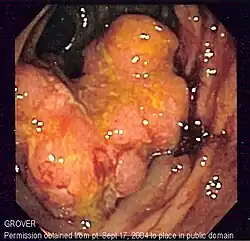

Imagem endoscópica do cancro de cólon, identificado no cólon sigmóide, em conjunto com doença de Crohn.

O cancro colorretal pode tomar muitos anos para desenvolver-se, e detecção do cancro nos estádios iniciais aumenta significantemente as chances de cura. O National Cancer Policy Board do Instituto de Medicina americano, estimou que modestos esforços para implementar métodos de detecção do cancro colorretal causaria uma queda de 29% em mortes de cancro em 20 anos. Porém, a taxa de indivíduos utilizando métodos de detecção precoce permanecem baixas.[45]